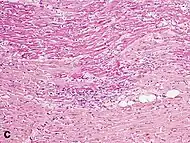

Although earlier changes can be discerned using electron microscopy, one of the earliest changes under a normal microscope are so-called wavy fibers.[21] Subsequently, the myocyte cytoplasm becomes more eosinophilic (pink) and the cells lose their transversal striations, with typical changes and eventually loss of the cell nucleus.[22] The interstitium at the margin of the infarcted area is initially infiltrated with neutrophils, then with lymphocytes and macrophages, who phagocytose ("eat") the myocyte debris. The necrotic area is surrounded and progressively invaded by granulation tissue, which will replace the infarct with a fibrous (collagenous) scar (which are typical steps in wound healing). The interstitial space (the space between cells outside of blood vessels) may be infiltrated with red blood cells.[20]

| Neutrophil infiltration | 12–24 h | 1–3 days | 5–7 days |  |

| Karyorrhexis of neutrophils | 1.5–2 days | 3–5 days |  | |

| Macrophages and lymphocytes | 3–5 days | 5–10 days (including 'siderophages') | 10 days to 2 months |  |

Differential diagnoses for myocardial fibrosis:

- Interstitial fibrosis, which is nonspecific, having been described in congestive heart failure, hypertension, and normal aging.[25]

- Subepicardial fibrosis, which is associated with non-infarction diagnoses such as myocarditis[26] and non-ischemic cardiomyopathy.[27]